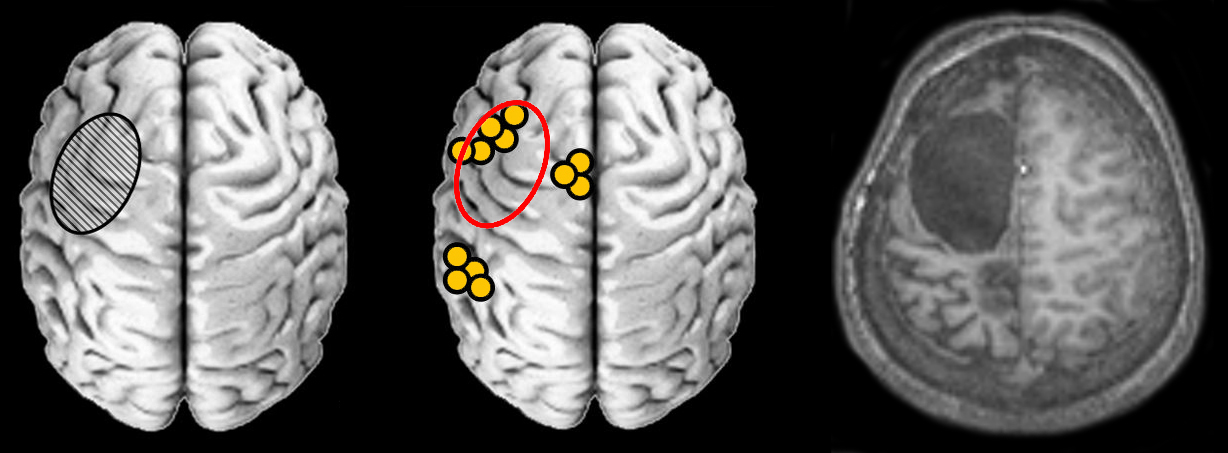

Neurosciences

Images et documents en rapport avec les articles

scenar5